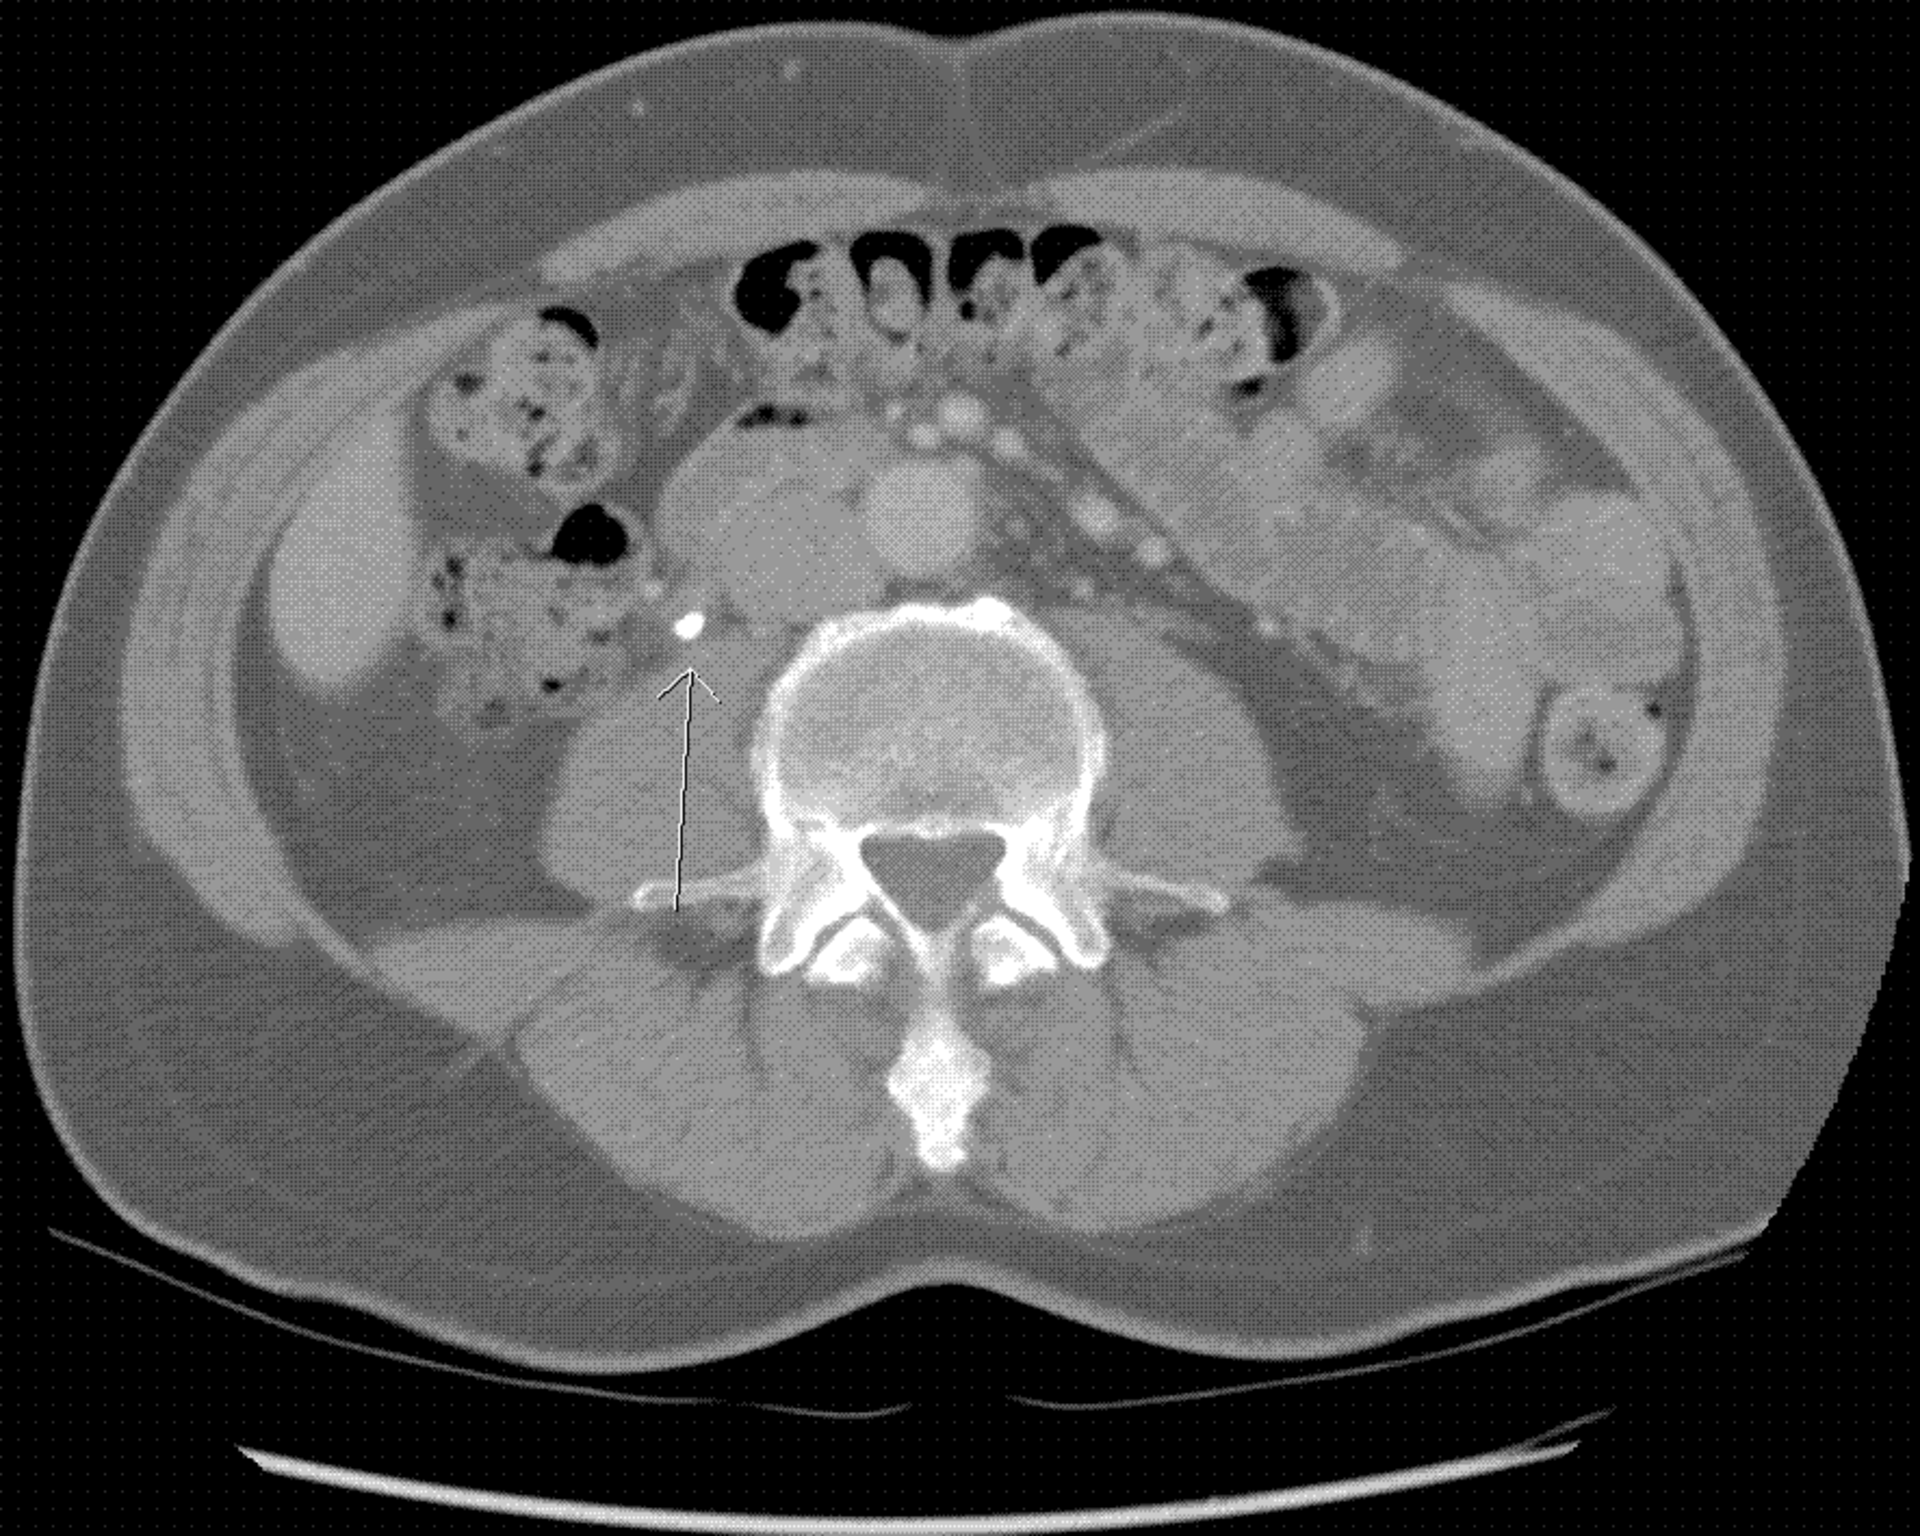

If you know me, you know that I believe in imaging technology and I am always interested in “practicing what I preach.” So, it should come as no surprise that several years ago when I was the unlucky recipient of a 6 mm kidney stone, I went to the to the Medical Records Department of the hospital after my ER visit, and requested a CD of my images! More on the significance of this later.

In relation to the CD of my kidney stone, it really served no medical purpose to have it. I took it with me on a follow up visit to my general practitioner, and he had no way (or interest) in viewing it! He had received the report from the Urologist, and that was all he needed. So, outside of the novelty of saying I have my images, what purpose does it serve?